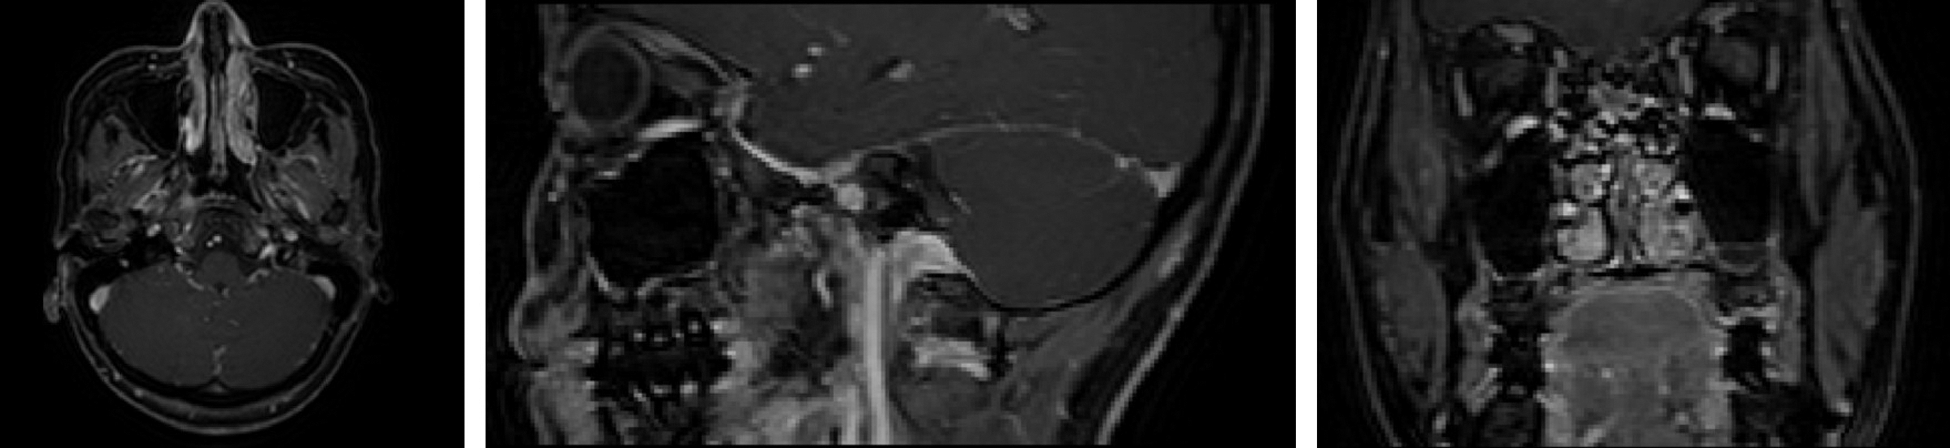

This experiment had been conducted using three-dimensional MRI images of 120 patients with NPC, which were from the same hospital. They were scanned by T1 High Resolution Isotropic Volume Examination (THRIVE [27]), which could obtain more obvious MRI tumor images than other MRI. The images have a voxel size of 0.6 × 0.6 × 3.0

Figure 3: Three views of NPC images (Left: top view; Middle: lateral view; Right: front view)